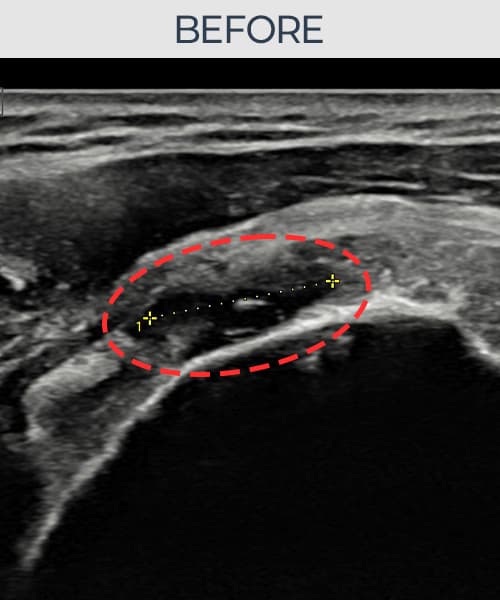

超音波検査にて腱板 関節面側部分断裂(14mm × 7mm (腱厚の約68%欠損))を確認。縫縮術施行後、腱の連続性が回復し、日常生活に復帰されました。

施術前

術前超音波にて腱板 関節面側部分断裂・肩棘上筋腱のエコー不連続と腱欠損(14mm × 7mm (腱厚の約68%欠損))を確認。術後超音波では断裂部位が再生組織で充填され、腱の連続性回復とエコーパターンの正常化が確認されました。

持続する肩痛で来院された患者様です。超音波検査にて腱板 関節面側部分断裂(欠損:14mm × 7mm (腱厚の約68%欠損))を確認し、超音波ガイド下で非手術的縫縮術を施行しました。術後は約4〜6週間のブレース装着の後、段階的なリハビリプログラムを実施。経過超音波で腱の連続性回復を確認し、患者様は無事に日常生活へ復帰されました。